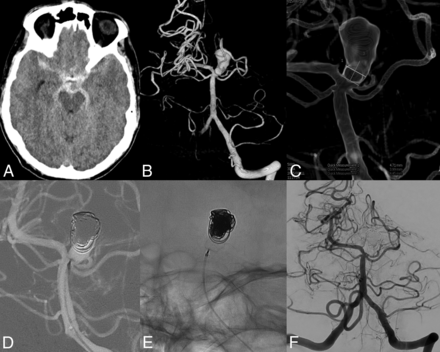

A 61-year-old man with a ruptured basilar tip aneurysm treated with the WEB and coils. A, CT scan with subarachnoid blood. B, 3D angiogram reveals a 13-mm basilar tip aneurysm. C, Neck measurement on a 3D angiogram. D and E, After placement of coils in the dome and a WEB-SL, 6 × 3 mm, in the neck. F, Three-month follow-up angiogram with complete occlusion.